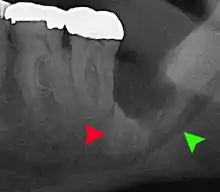

For partially impacted teeth in those over 20 year of age, the most common pathology seen, and the most common reason for wisdom teeth removal, is pericoronitis or infection of the gum tissue over the impacted tooth. The bacteria associated with infections include Peptostreptococcus, Fusobacterium, and Bacteroides bacteria. The next most common pathology seen is cavities or tooth decay. Fifteen percent of people with retained wisdom teeth exposed to the mouth have cavities on the wisdom tooth or adjacent second molar due to a wisdom tooth. The rate of cavities on the back of the second molar has been reported anywhere from 1% to 19% with the wide variation attributed to increased age.[12]

In five percent of cases, advanced periodontitis or gum inflammation between the second and third molars precipitates the removal of wisdom teeth.[5]:141[6] Among patients with retained, asymptomatic wisdom teeth, roughly 25% have gum infections (periodontal disease).[13]:ch13 Teeth with periodontal pockets of greater than 5mm have tooth loss rates that start at 10 teeth lost per 1000 teeth per year at 5mm to a rate of 70 teeth lost per year per 1000 teeth at 11mm.[14]:57 The risk of periodontal disease and caries on third molars increases with age with a small minority (less than 2%) of adults age 65 years or older maintaining the teeth without caries or periodontal disease and 13% maintaining unimpacted wisdom teeth without caries or periodontal disease.[15] Periodontal probing depths increase over time to greater than 4 mm in a significant proportion of young adults with retained impacted wisdom teeth which is associated with increases in serum inflammatory markers such as interleukin-6, soluble intracellular adhesion molecule-1 and C-reactive protein.[16]

Long-term complications can include periodontal complications such as bone loss on the second molar following wisdom teeth removal. Bone loss as a complication after wisdom teeth removal is uncommon in the young but present in 43% of those of 25 years of age or older.[21] Injury to the inferior alveolar nerve resulting in numbness or partial numbness of the lower lip and chin has reported rates that vary widely from 0.04% to 5%.[21] The largest study is from a survey of 535 oral and maxillofacial surgeons in California, where a rate of 1:2,500 was reported.[25]

Coronectomy

Coronectomy is a procedure where the crown of the impacted wisdom tooth is removed, but the roots are intentionally left in place. It is indicated when there is no disease of the dental pulp or infection around the crown of the tooth, and there is a high risk of inferior alveolar nerve injury.[31]